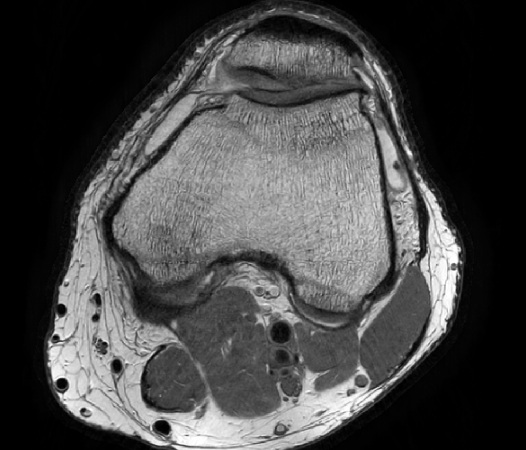

Compressed SENSE is the latest Philips MRI acceleration method, based on our industry leading dStream architecture. Compressed SENSE further expands the performance of dS SENSE, making MRI scans up to an additional 50% faster*, with virtually identical image quality. Alternatively, Compressed SENSE can increase the image resolution up to 40% within the same scan time. Compressed SENSE can be applied to all anatomies and works for both 3D as well as for 2D MRI acquisitions, making it a powerful asset for almost all clinical MRI exams.

Compressed SENSE is the Philips implementation of the compressed sensing principle. It combines dS SENSE, our industry leading parallel imaging method, with compressed sensing. As a result, it can reduce the scan times by up to 50% compared to current examinations without Compressed SENSE. Philips Compressed SENSE is unique for various reasons: